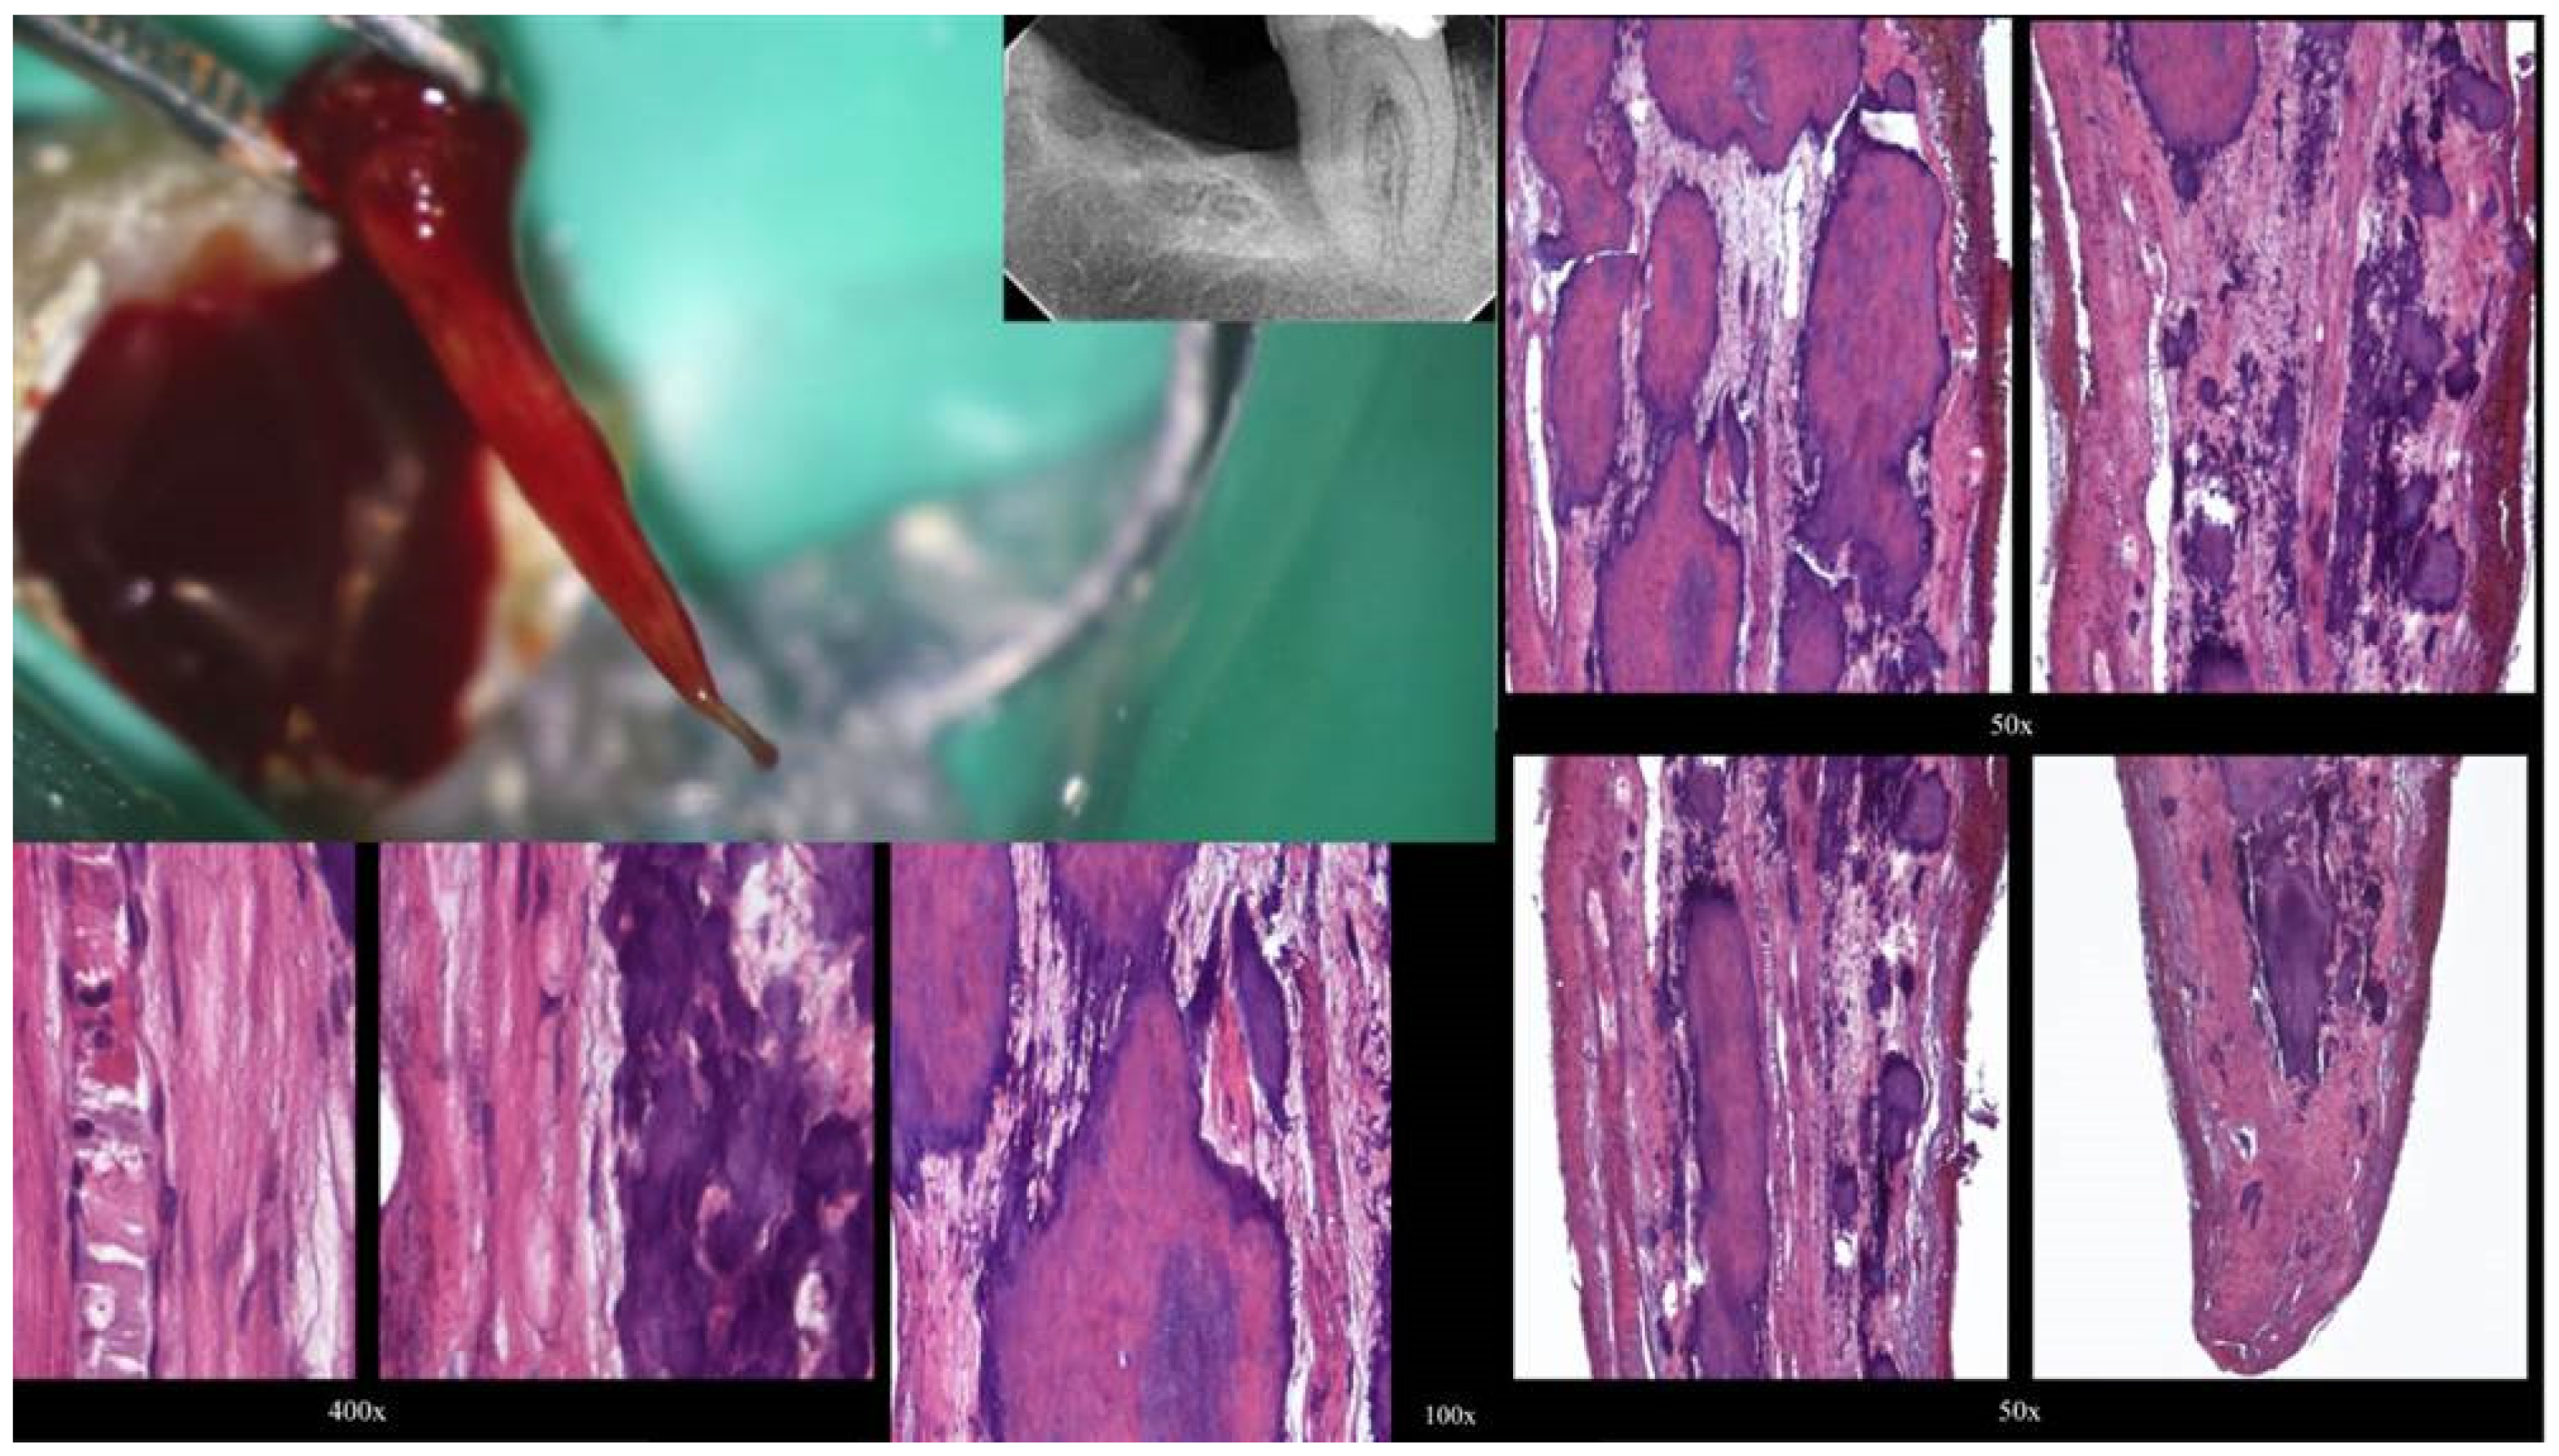

Figure 3.

Histological images of the calcified vital pulp tissue that was removed during the root canal treatment of a second mandibular molar with deep periodontal distal lesion suffering from symptomatic irreversible pulpitis. Notice the linear calcified nodules formed along the root pulp vessels. (hematoxylin eosin staining) (Histological images courtesy of prof. Domenico Ricucci).